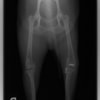

術前側面像

術前正面像

術前に25°であったTPAは、TPLO実施により7°に矯正されました。症例の歩行状態は良好です。